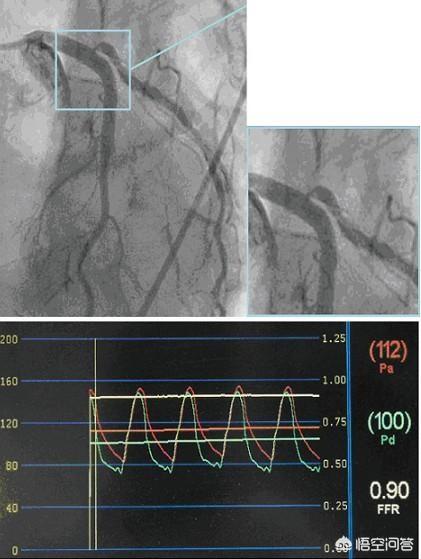

しかし、これはすべて主観的な判断であり、定性的な分析ができる客観的な検査はあるのでしょうか?FFR(Flow Reserve Fraction)はより客観的な検査です。FFRが80%以上であれば心筋虚血はなく、ステント留置の必要はありません。FFRが75%未満であれば心筋虚血があり、ステント留置が必要です。

そのため、ステントを入れるか入れないかは、臨床症状と冠動脈造影を組み合わせる必要があり、それでも病変が虚血しているかどうかわからない場合は、より客観的な証拠を得るためにFFR検査をお勧めします。